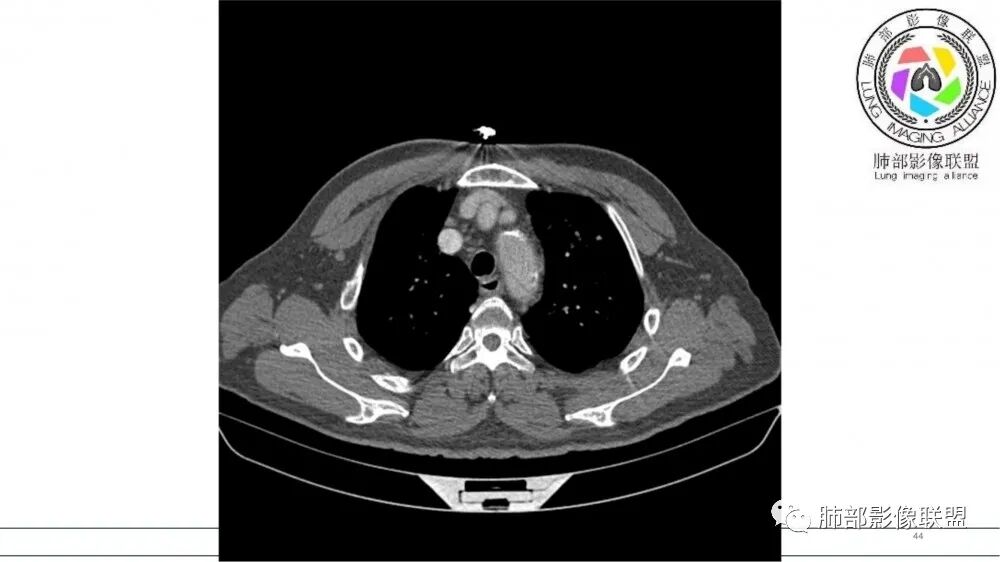

左肺上叶前段支气管内铸形生长软组织影,增强后均匀强化,远侧见斑片状磨玻璃影。考虑恶性病变,粘表?粘液腺?

左肺上叶前段支气管杵状指样扩张,内见实性组织阻塞性,并强化明显,边缘饱满,周边多发小斑点影,小花小草征,老年男性,长期吸烟史,方向恶性,首选支气管内浸润鳞Ca可能性大。

老年男性,肺气肿,吸烟史,左肺上支气管腔内铸型高密度影,呈指套状,远端多发树芽,增强不均匀强化,考虑鳞癌,鉴别小细胞癌

B3指套征,常规不是鳞癌就是ABPA,有强化丶血管造影征,倾向于鳞癌

老年男性,长期吸烟史。左上肺前段沿支气管走形的指套样病变,增强可见病灶强化(排除结核、ABPA(也无气喘症状)),远端多发点状高密度影。考虑恶性肿瘤,鳞癌可能性大。

指套征,扩张支气管内软组织强化,远侧肺野阻塞性炎,纵隔、左肺门肿大淋巴结;老年男性,吸烟,考虑鳞癌,鉴别小

指套征:是影像征象,胸部平片表现为手指状密度增高影,以肺门为中心呈放射状分布,CT显示扩张支气管内低密度黏液栓形成或实性病变,呈管状、树枝状或卵圆形密度增高影;支气管扩张伴近端梗阻时,扩张支气管内部黏液分泌物不能排出而形成。可以伴随远端空气潴留征、阻塞性炎症。

研究报道,中心型 SCLC 经 CT 扫描后通常支气管表现为鼠尾样狭窄,肺门或纵隔肿块明显,由于肿块沿管壁生长表现为顺延支气管形态的不规则形状。病灶相对特征性影像学表现比如鸭蹼状、腊肠状、葫芦状及葡萄状改变,可以出现血管包埋,很少有空洞、空泡,较少引发肺不张,阻塞性炎症成都较轻。与一般肺癌比较,恶性程度高,侵袭力强、病灶很小就容易远处转移!Herzberg 等[19]研究指出,20%以上 SCLC 倍增时间短,预后不良。